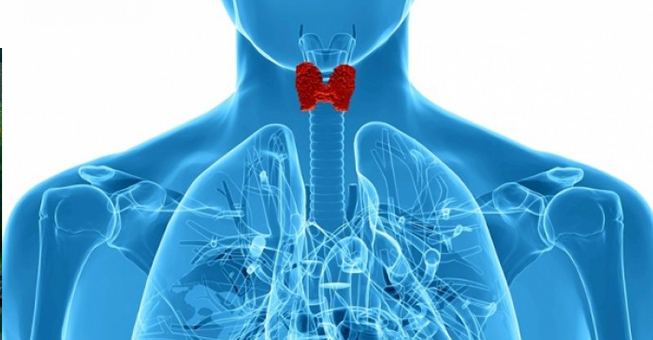

Πώς θα καταλάβετε ότι έχει πρόβλημα ο θυρεοειδής σας

Ο θυρεοειδής σας είναι ένας αδένας σε σχήμα πεταλούδας στον λαιμό σας, ακριβώς πάνω από την κλείδα σας.Είναι ένας από τους ενδοκρινείς αδένες του οργανισμού, που παράγουν ορμόνες. Οι θυρεοειδικές ορμόνες ελέγχουν τη λειτουργία πολλών δραστηριοτήτων στο σώμα σας.Αυτές περιλαμβάνουν το πόσο γρήγορα μπορείτε να κάψετε θερμίδες και πόσο γρήγορα χτυπάει η καρδιά σας.